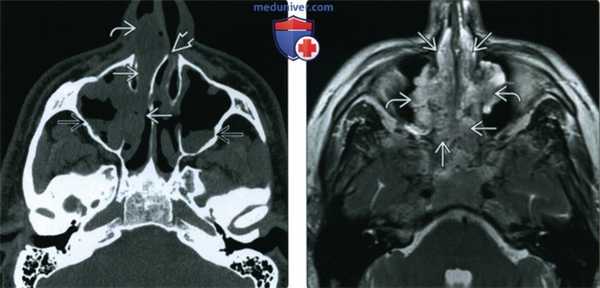

(Слева) При корональной «костной» КТ у девочки 14 лет с муковисцидозом (МВ) определяются типичные признаки ПНП, в т.ч. снижение пневматизации ячеек решетчатой кости справа за счет полиповидного материала, распространяющегося также в полость носа, и доброкачественное ремоделирование костей. Обратите внимание на большое мукоцеле решетчатой кости слева с распространением в орбиту и гипоплазию правой лобной пазухи.

(Справа)При аксиальной «костной» КТ у пациента с МВ визуализируется крупный полип в полости носа справа, связанный со средней носовой раковиной. Выраженная гипоплазия основных пазух часто наблюдается при МВ.

(Слева) При аксиальной КТ без КУ визуализируется большой полип, заполняющий полость носа справа, и выбухающий из правой ноздри. Обратите внимание на доброкачественное ремоделирование костей и смещение влево костной носовой перегородки. Уровни «жидкость-газ» с пузырьками газа в верхнечелюстных пазухах неспецифичны и могут быть обусловлены воспалительным компонентом при остром синусите.

(Справа) При аксиальной MPT Т2ВИ у пациента с тяжелым полипозом визуализируются множественные гиперинтенсивные полипы, заполняющие полость носа и внутренние отделы верхнечелюстных пазух.